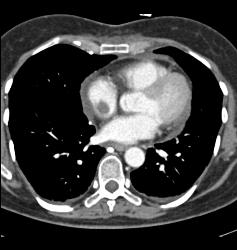

SVC Occlusion With Huge Collaterals and Thrombus Into Right Atrium